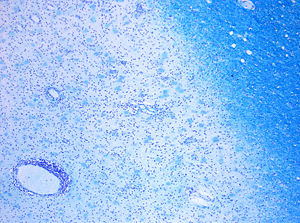

It is known that a repair process, called remyelination, takes place in early phases of the disease, but the oligodendrocytes that originally formed a myelin sheath cannot completely rebuild a destroyed myelin sheath. The newly-formed myelin sheaths are thinner and often not as effective as the original ones. Repeated attacks lead to successively fewer effective remyelinations, until a scar-like plaque is built up around the damaged axons, according to four different damage patterns. The central nervous system should be able to recruit oligodendrocyte stem cells capable of turning into mature myelinating oligodendrocytes, but it is suspected that something inhibits stem cells in affected areas.